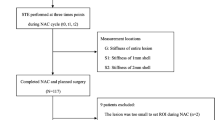

SWE studies were conducted for each patient at three time points: before initiation of NACT, at the mid-course of NACT, and after completion of NACT but prior to surgery. A flow diagram of the study population is summarized in Fig. 1.

There are some limitations in this study. Firstly, the sample size was relatively small; moreover, as shown in the flowchart, some patients did not complete all three visits for the SWE studies, leading to some missing data. However, the leave-one-out cross-validation has been applied to compensate for the sample number limitation. Secondly, this is a one-center study. Thus, a multicenter study with a larger population is required to further investigate the role of SWE parameters in NACT response prediction.